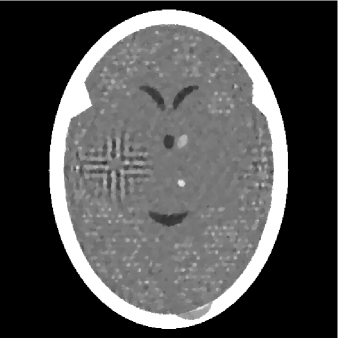

Figure 1 shows the phantom used in our study, which is a digitized image whose TV is 984. The phantom corresponds to a cross-section of a human head (based on (HERM09, , Figure 4.6)). It is represented by a vector with components, each standing for the average x-ray attenuation coefficient within a pixel. Each pixel is of size mm2. The values of the components are in the range of , however, the display range used here was much smaller, namely . The mapping between the two ranges is such that any value below is shown as black and any value above is shown as white with a linear mapping in-between. We used this display window for all images presented here.

Data were collected by calculating line integrals through the digitized head phantom in Figure 1 using sets of equally rotated (in degrees increments) parallel lines, with lines in each set spaced at mm from each other. Each line integral gives rise to a linear equation and represents a hyperplane in . The phantom itself lies in the intersection of all the hyperplanes that are associated with these lines, and it also satisfies the box constraints in (10). The total number of linear equations is , making our problem underdetermined with unknowns (the intersection of all the hyperplanes is in an at least -dimensional subspace of ). In the comparative study, we first applied the PSM and then the SM to these data as follows.